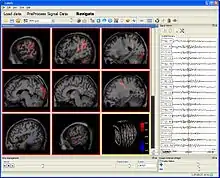

GIMIAS GUI includes multislice view of multimodal biomedical images and signal navigation tools | |

- Biomedical data visualization in 2D and 3D: multiplanar reformation, ortho slice view, multi slice view, volume rendering, X-ray rendering, maximum intensity projection

- Other additional tools for image segmentation, mesh manipulation and signal navigation.[5]